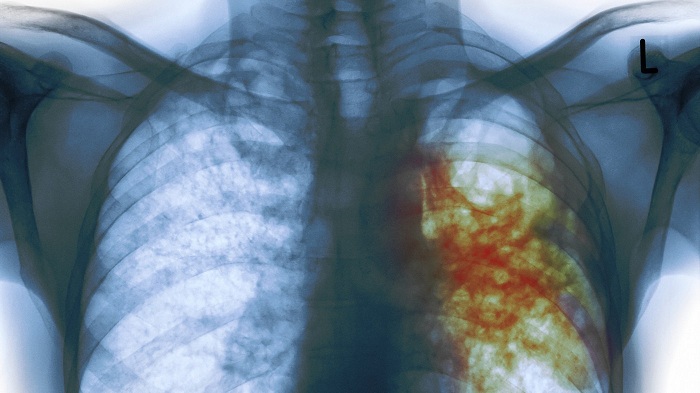

Tuberculosis is caused by the bacterium Mycobacterium tuberculosis, which spreads through the air when a person with active TB coughs, sneezes, or speaks. The disease remains among the top ten killers globally and is a leading opportunistic infection among people living with HIV.